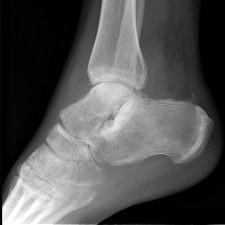

问题 男,28岁,踝部肿痛,结合图像,最可能的诊断是 ( ) .

选项 A、跟骨结核 B、踝关节类风湿关节炎 C、跟骨骨髓炎 D、踝关节滑膜炎 E、未见异常

答案 C